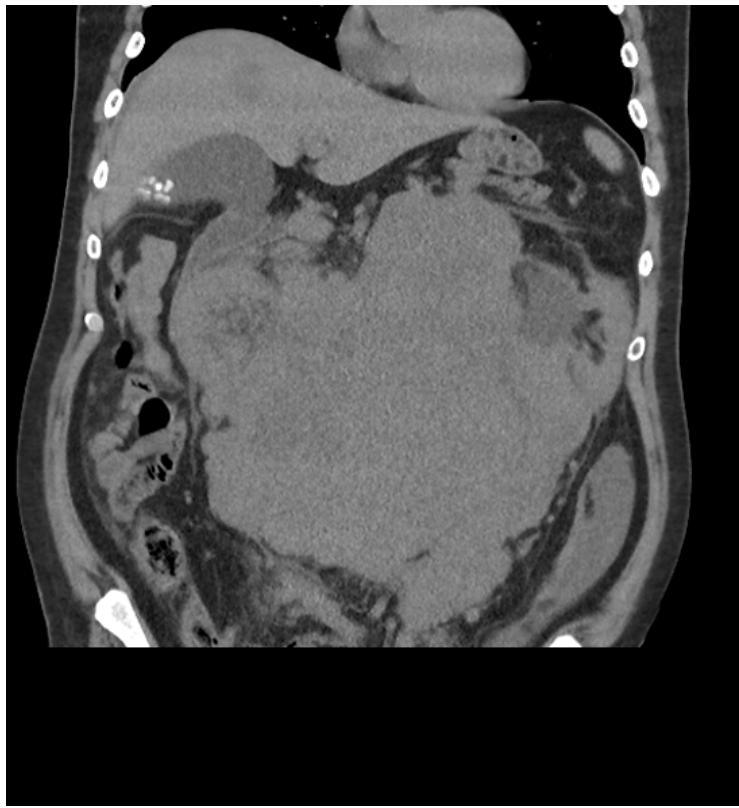

Harsh Bansal et al. Imaging Modalities for Preoperative Staging of Rectal Cancer in Developing Countries : A Comparative Study of F-FDG PET/CT And MRI